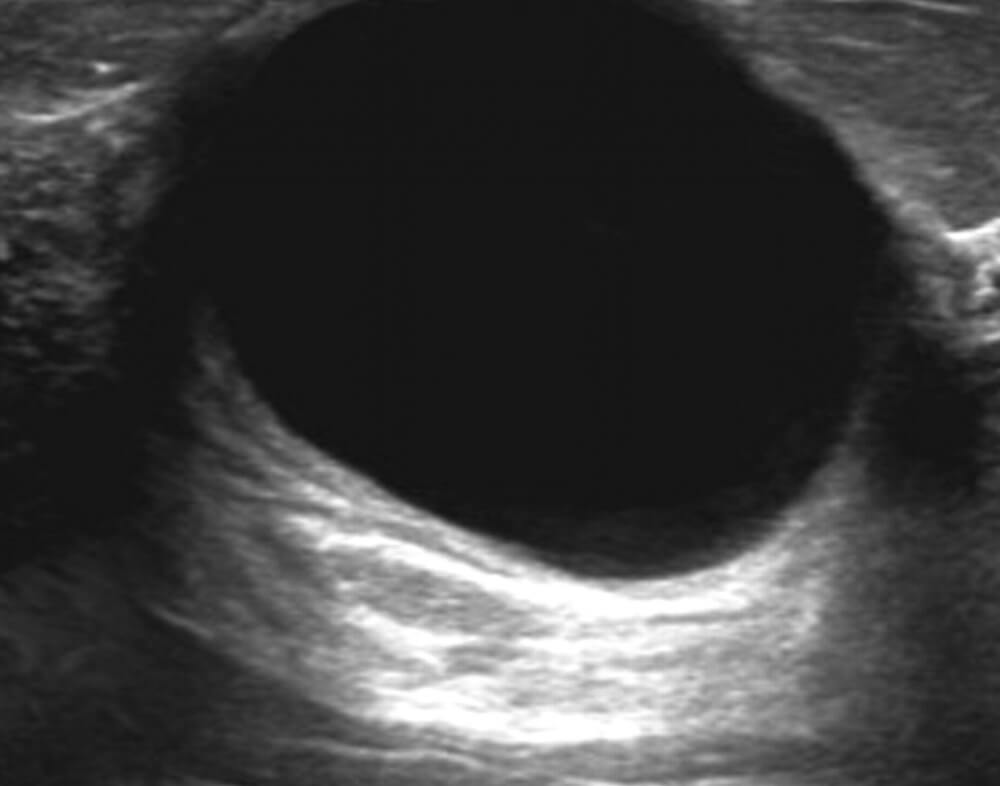

Οι απλές κύστεις, πρακτικά, είναι μικρά «σακουλάκια» μέσα στο μαστό που περιέχουν υγρό.

Μερικές φορές μπορεί να έχουν μεγαλύτερο μέγεθος ώστε να είναι ψηλαφητές ή ακόμη και ορατές σαν διογκώσεις στο μαστό.

Δεν σχετίζονται με την ανάπτυξη κακοήθειας και δεν χρειάζονται καμία θεραπεία.